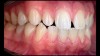

(9.) Preoperative esthetic case documentation using a smartphone and an EALS device.

Figure 9

(10.) Preoperative esthetic case documentation using a smartphone and an EALS device.

Figure 10

(11.) Preoperative esthetic case documentation using a smartphone and an EALS device.

Figure 11